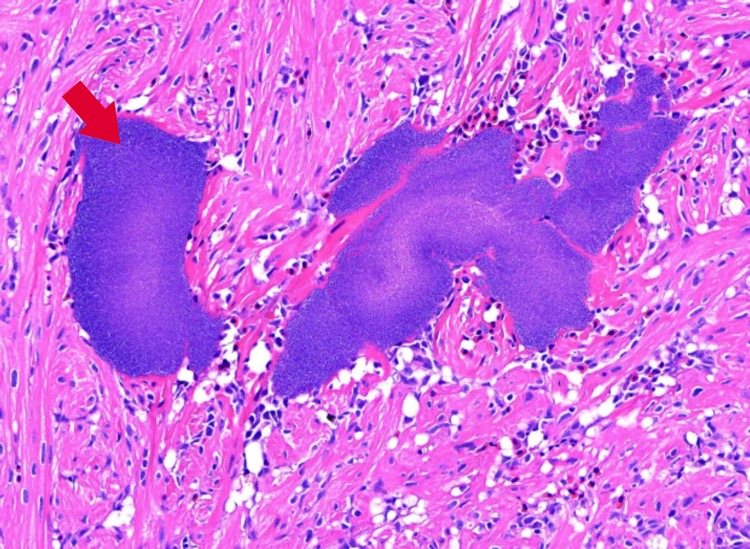

II.5. Bacterial Kidney Disease (BKD, Renibacterium salmoninarum)

Patogenia: coloniza macrófagos, evade inmunidad, produce proteína p57 que suprime respuesta inmune; curso crónico.Histopatología: granulomas en riñón con necrosis central, infiltrado de macrófagos y células gigantes multinucleadas.

Histoquímica/IHQ: Gram positivo intracelular; IHQ mejora diagnóstico en infecciones tempranas.